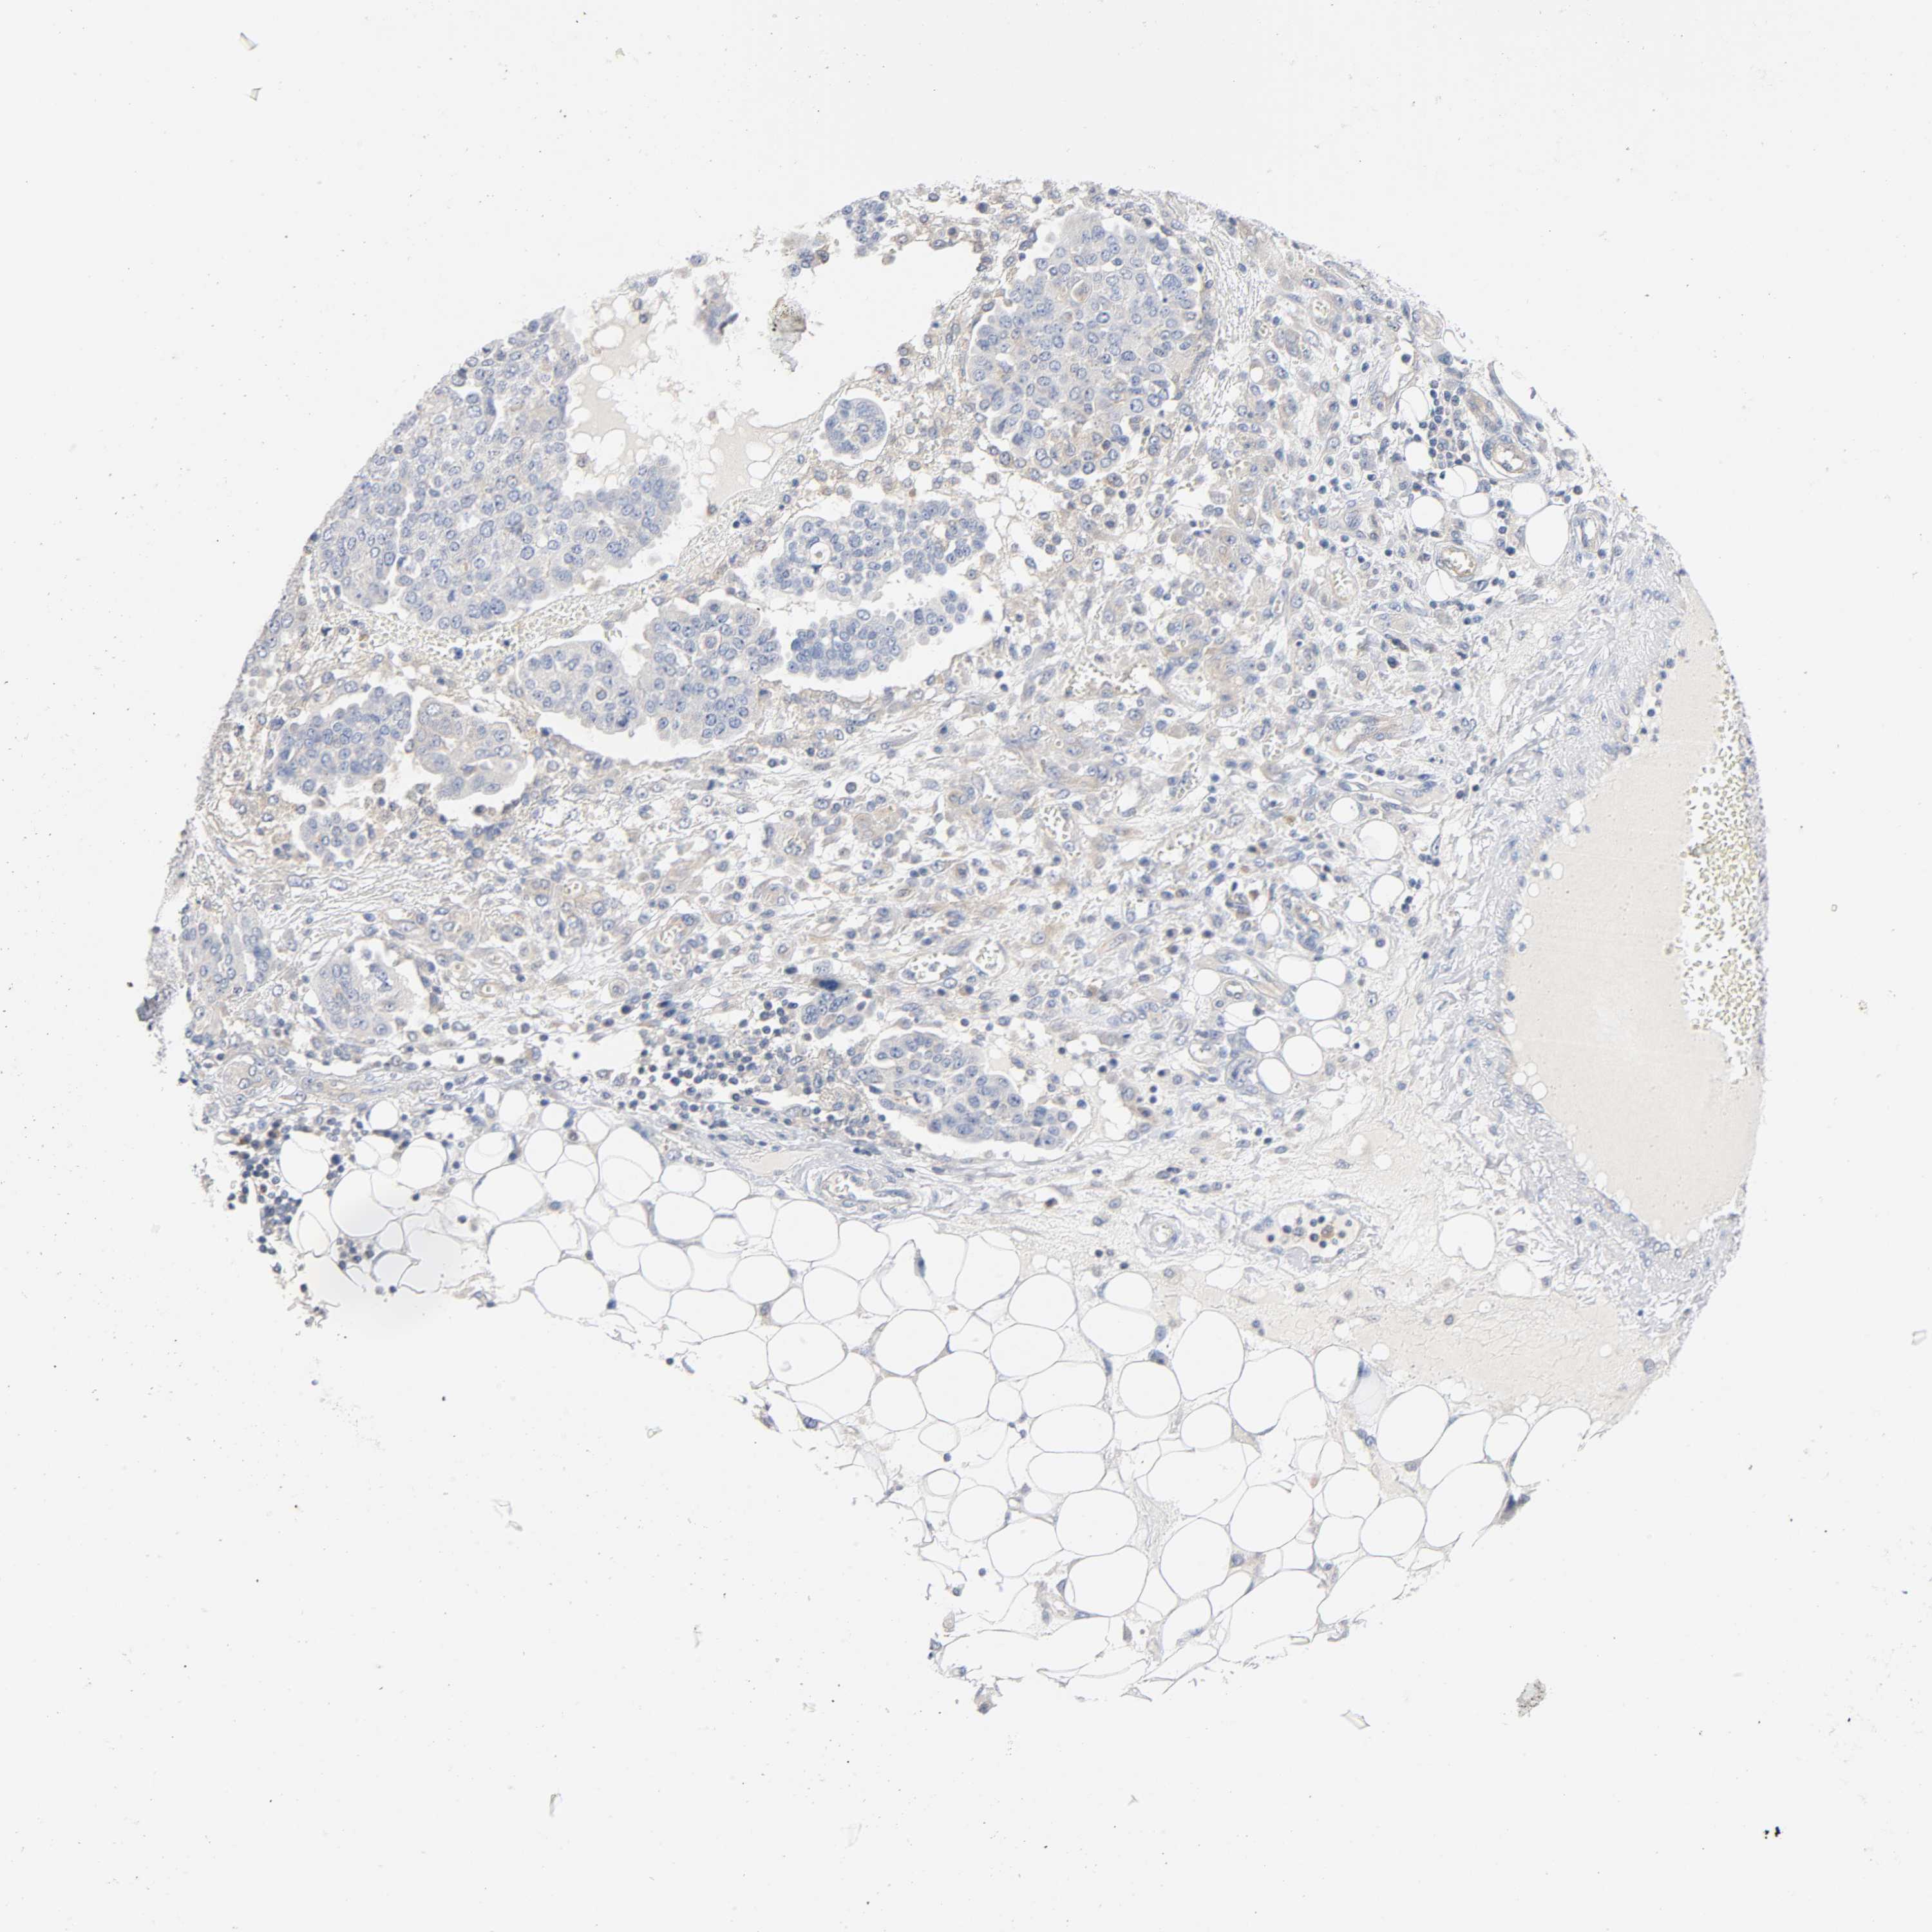

OVARIAN CANCER - Protein expressioni

A mouse-over function shows sample information and annotation data. Click on an image to view it in a full screen mode. Samples can be filtered based on level of antibody staining by selecting one or several of the following categories: high, medium, low and not detected. The assay and annotation is described here.

Note that samples used for immunohistochemistry by the Human Protein Atlas do not correspond to samples in the TCGA dataset.

Antibody stainingi

Antibody staining in the annotated cell types in the current human tissue is reported as not detected, low, medium, or high, based on conventional immunohistochemistry profiling in selected tissues. This score is based on the combination of the staining intensity and fraction of stained cells.

Each image is clickable and will lead to virtual microscopy that enables deeper exploration of all samples and also displays staining intensity scores, fraction scores and subcellular localization as well as patient and tissue information for each sample.

Antibody CAB004494

Staining

High

Medium

Low

Not detected

Intensity

Strong

Moderate

Weak

Negative

Quantity

>75%

75%-25%

<25%

None

Location

Nuclear

Cytoplasmic/membranous

Cytoplasmic/membranous,nuclear

Cystadenocarcinoma, serous, NOS

Carcinoma, endometroid

Carcinoma, NOS

Cystadenocarcinoma, mucinous, NOS